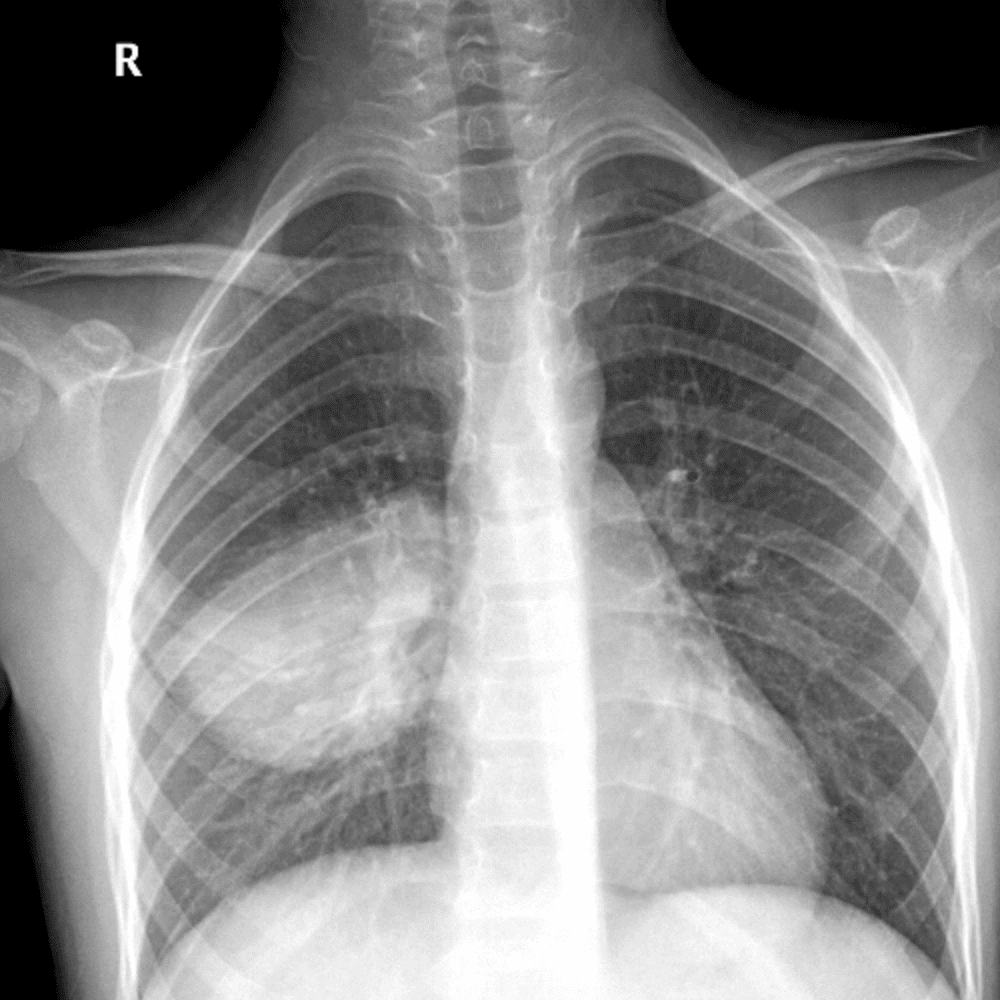

Peds Chest

Practice

Simulates call by including subtle or difficult cases and some normals.

50 cases